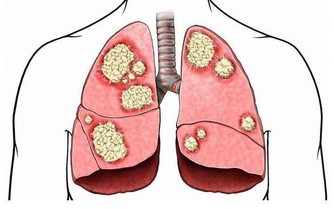

腦血栓,離我們遠嗎?

腦血栓不但影響患者身心健康嚴重的甚至導致癱瘓。